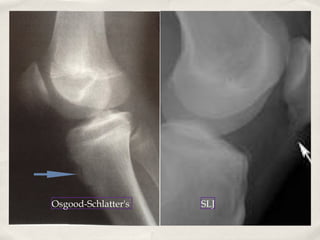

Overuse Problems: Apophsitis

Traction apophysitis is very common around the knee

Osgood Schlatter's: tibial tuberosity

Sindig-Larsen-Johannsen: Inferior pole patella

Occurs around age 10-15, earlier in girls

✤

Often very active in sports

✤   More common in boys

+/- growth spurt

Relative extensor mechanism inflexibility

Associated with jumping squatting, cutting sports

Osgood-Schlatter's   SLJ